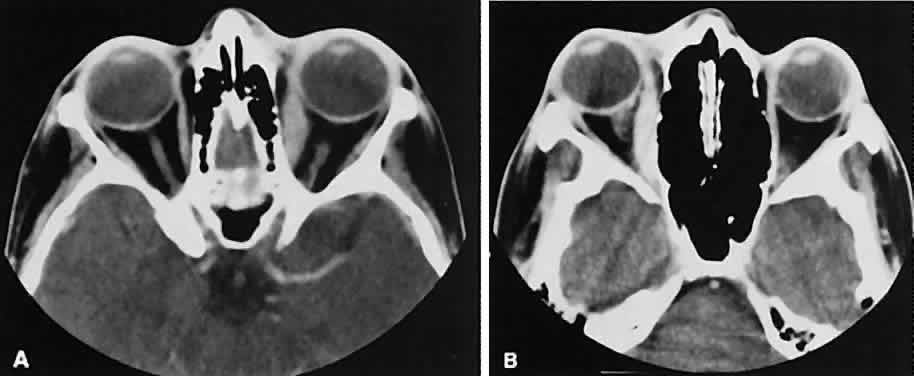

| Abnormal size of the optic nerve and sheath on the CT scan usually is pathologic. Rothfus

and colleagues49 suggested a differential approach based on high-resolution CT morphology. An enlarged optic nerve also is associated with an age-related differential diagnosis. Most gliomas are found in children, whereas optic nerve sheath meningiomas tend to afflict adults, primarily women. Nevertheless, there are exceptions for each. Optic nerve gliomas are associated with neurofibromatosis. A prospective study determined that a child with known neurofibromatosis has a 15% chance of having a glioma of the anterior visual pathway. Conversely, a child with an optic nerve glioma has a 25% chance of having neurofibromatosis.50 Although an optic nerve meningioma can occur in association with neurofibromatosis, particu-larly NF-2,51 the association is not as firmly established as with gliomas. It is uncommon but well-established that optic nerve meningiomas can occur during childhood. Not only can they create confusion regarding differentiation from optic nerve glioma, but, most important, they behave in a more aggressive fashion.52 The CT evaluation of optic nerve lesions is facilitated by the use of 1.5-mm axial slices and intravenous contrast.49 Gliomas usually appear as a fusiform enlargement with sharp delineation from the surrounding tissue due to circumscription by an intact dura (Fig. 10). Kinking and buckling of the optic nerve along with infarctive cysts are typical findings in an optic nerve glioma. Bilaterality and intracranial involvement of the anterior visual pathway also may be noted. The radiographic signature of an optic nerve meningioma is more variable (Fig. 11). The optic nerve shadow tends to be diffusely enlarged, with irregular expansion along the optic nerve. Jakobiec and colleagues53 found diffuse enlargement of the optic nerve with apical expansion to be the most frequent pattern. Calcification within the optic nerve shadow, which is unusual in optic nerve gliomas, is common with optic nerve meningioma. The irregular excrescent margins most likely signify extradural invasion into the adjacent orbital soft tissues. A central linear lucency extending the length of the optic nerve shadow also is a typical finding of an optic nerve meningioma.49 These two lesions represent the most frequent tumors affecting the optic nerve. Other reported tumors include hemangioblastoma, leukemic infiltration, and involvement by metastatic disease. Enlargement of the dural sheath around the optic nerve, an optic nerve meningocele, can be confused with a tumor.54 The radiographic procedure of choice for evaluating suspected optic nerve lesions is MRI with gadolinium and high-resolution, fat-suppression techniques. ORBITAL TUMORS In a patient with an orbital mass, CT can show not only the mass but also other valuable information such as shape, location, consistency, intralesional calcium, and effect on surrounding structures.55 Contrast enhancement offers some ideas about vascularity. VASCULAR TUMORS The vascular tumors under consideration are capillary hemangioma, cavernous hemangioma, lymphangioma, and hemangiopericytoma. Capillary hem-angiomas and lymphangiomas are benign infiltrativetumors seen in a pediatric population. Capillary hemangiomas have a homogeneous consistency, display intense uniform contrast enhancement, and do not usually displace any orbital structures (Fig. 12). Phleboliths are a characteristic finding in hemangiomas and, when present, are virtually pathognomonic of this diagnosis.56 Lymphangiomas have a cystic component, which, on occasion, may hemorrhage into itself, accounting for rapid onset of symptoms and clinical/radiographic evidence of mass effect (Fig. 13). In all likelihood, scans require sedation for an adequate study. Thin (1.5-mm) axial views with computer reformatting for coronal views along with contrast enhancement should provide an adequate study.